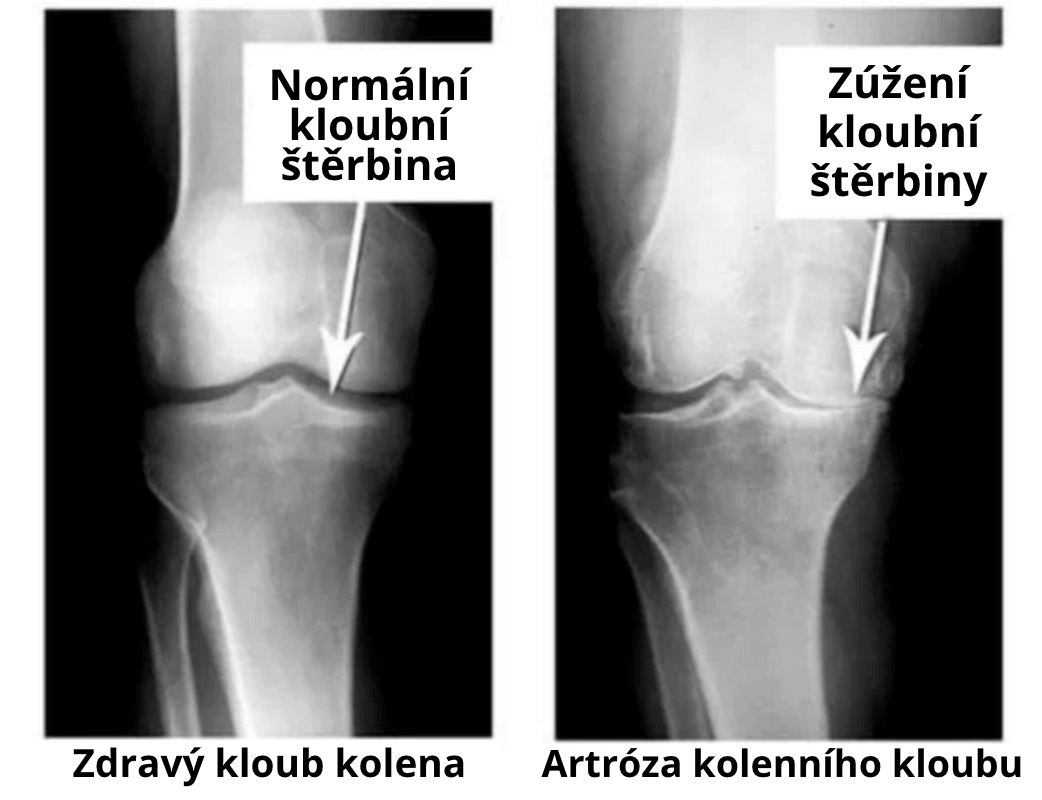

Podívejte se na tyto snímky, vidíte, že na pravém snímku chybí kloubní štěrbina, kosti se třou o sebe a způsobují silnou bolest. A tento proces je velmi obtížné zastavit! Za pár let bude člověk invalidní a nebude schopen se uživit.

MUDr. Ladislav Šenolt: Především se jedná o zranění a závažnou zátěž. Nadváha také vyvíjí silný tlak na klouby. Sedavý životní styl, stres, množství soli a cukru v potravinách — to vše zjemňuje tkáň chrupavky, opotřebovává ji a ztenčuje. Z každého nového pohybu se chrupavka stírá a deformuje, kosti se o sebe začnou třet, což způsobí nesnesitelnou bolest .